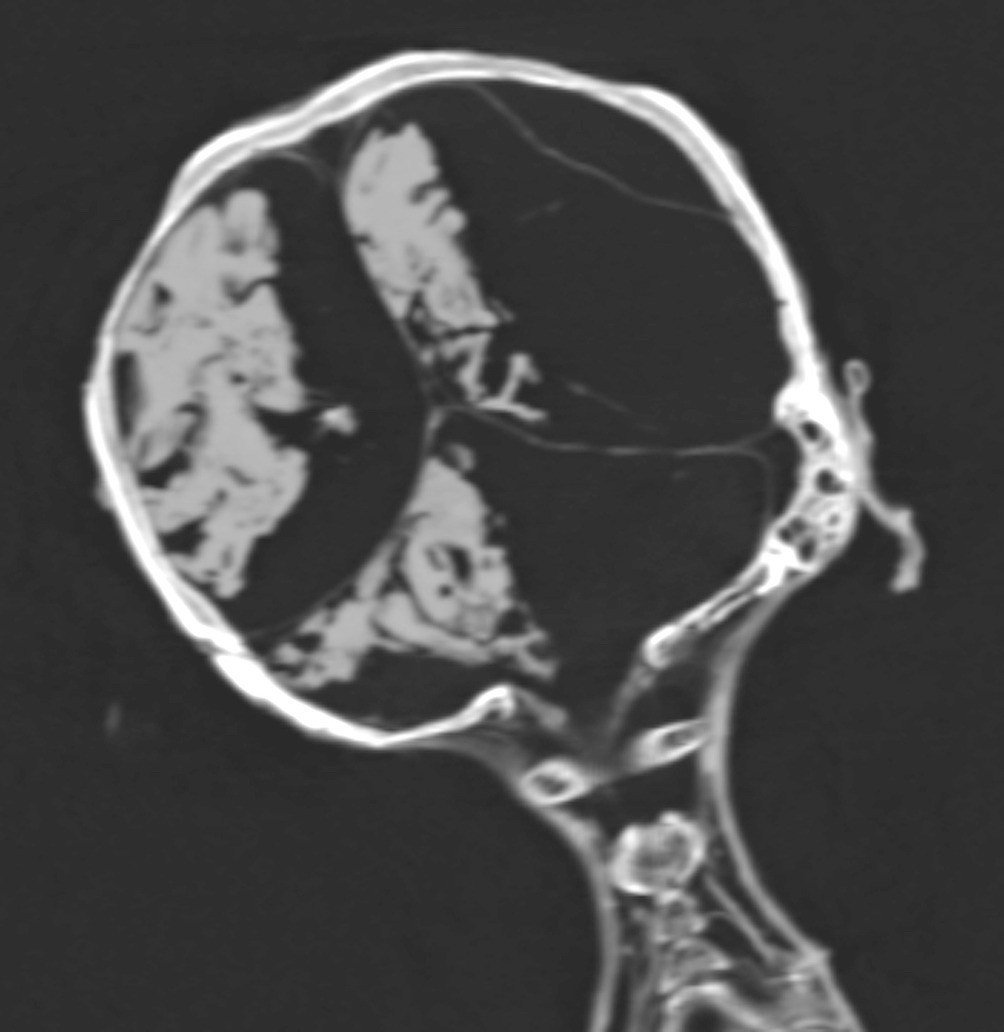

Sau nhiều năm nghiên cứu, các chuyên gia tìm ra câu trả lời. Theo nhà Ai Cập học Zahi Hawass và giáo sư X-quang học Sahar Saleem tại Đại học Cairo, "người phụ nữ la hét" qua đời đột ngột vì đau tim.

Người phụ nữ này bị xơ vữa động mạch vành trái và phải, động mạch cổ, động mạch chủ bụng, động mạch chậu gốc và chi dưới.